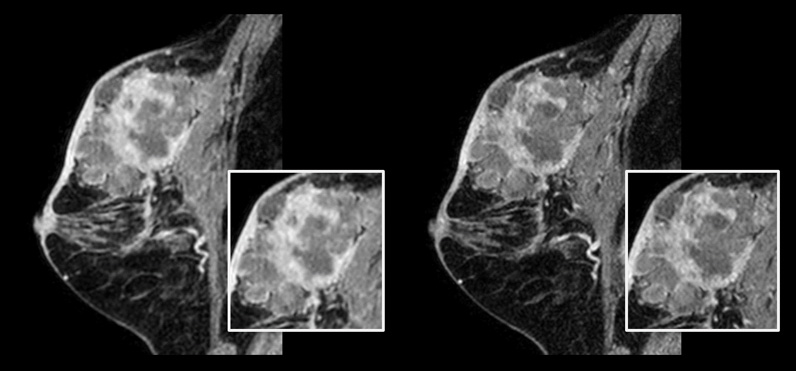

In conventional MRI scan techniques, high resolution imaging can involve long scan times which may be difficult for patients experiencing pain and discomfort. Long scan times can also make it difficult to fit high resolution imaging into acceptable MRI scan time slots for busy departments. Compressed SENSE enables fast 3D submillimeter (0.7 mm or less) isotropic images in less than 5 minutes to help diagnose challenging patients and anatomies.

Patient with breast cancer.

On the left: Conventional 3D mDIXON XD scan with 1.0 mm isotropic voxel size in a scan time of 2:22 min

On the right: Compressed SENSE 3D mDIXON XD scan with 0.8 mm isotropic voxel size in a scan time of 2:21 min.

Courtesy: Kurashiki Central Hospital, Okayama. Japan

In breast scanning, high resolution is important to help me identify very small mammary lesions, so, we need high spatial resolution in 2D T1- and T2-weighted images, as well as a short scan time. Compressed SENSE has allowed us to increase spatial resolution, which benefits our diagnostic confidence.”

Dr. Takashi Koyama, MD, PhD, Diagnostic Radiologist and Director of the Department of Radiology Center and Diagnostic Radiology, Kurashiki Central Hospital, Japan